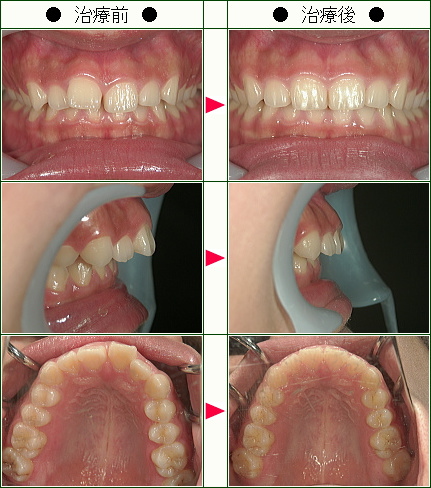

歯のデコボコ矯正の治療症例解説<上だけの症例>(19歳以下)--部分矯正--その4

☆歯のデコボコ矯正症例[R.Y様 13歳 女性]